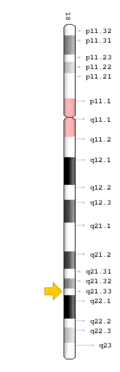

TCIRG1 mutation

The TCIRG1 gene is present in chromosome locus 11q13, which encodes for the a3 subunit of vacuolar H+ ATPase (V-ATPase) that is unique to osteoclasts.[12] The a3 subunit is responsible in anchoring the vacuolar proton pump to the ruffled membrane of osteoclasts.[9] The V-ATPase is important in mediating the transport of hydrogen ions into the resorption lacunae, which is a pit on the bone surface enclosed by the osteoclast for bone resorption. The accumulation of ions in the lacuna facilitates the decomposition of hydroxyapatite crystals by creating an acidic environment, resulting in bone resorption.[12]